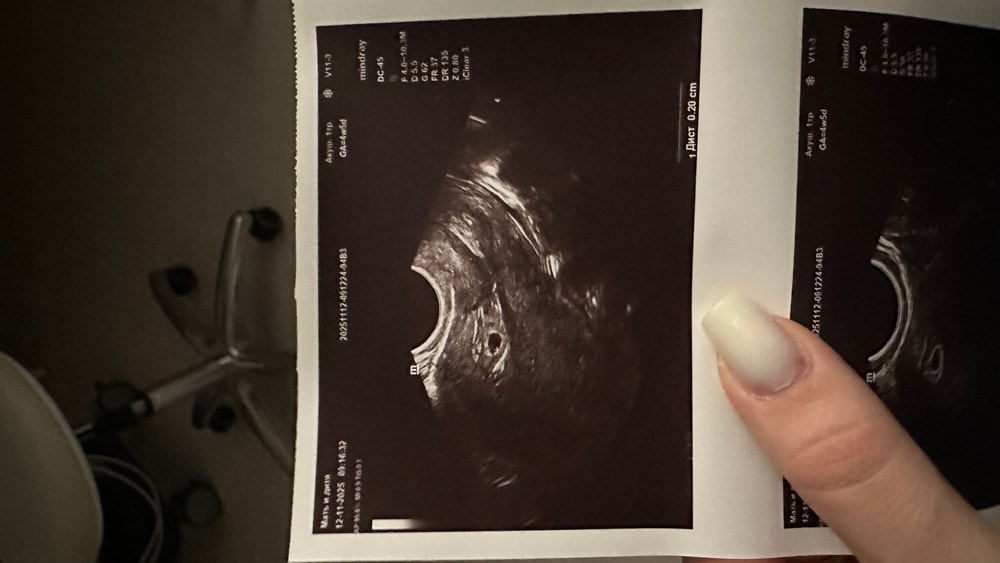

по узи 4-5 недель,плодное яйцо в матке,гематом нет.